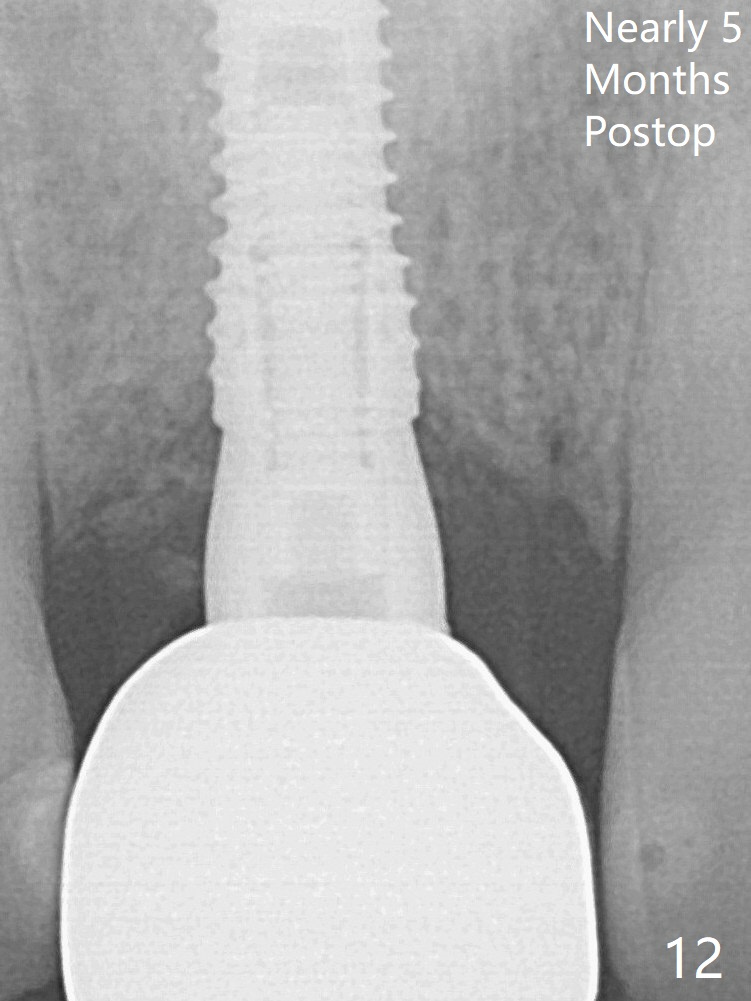

The initial osteotomy depth is 16 mm (Fig.5); the trajectory is going to be adjusted as shown by arrows. The trajectory improves when a 3.8x15 mm dummy implant is placed (Fig.6). The definitive implant (3.8x16 mm) appears to be placed at an appropriate level (Fig.7). A 4.5x3 mm temporary abutment is inserted for an immediate provisional. As routine, Vera Graft is placed in the buccal gap. Although the provisional. is unstable, there is no bone loss 2 months 20 days postop (Fig.9). Because of the loose provisional (detachment from the underlying temporary abutment), impression is taken earlier (3 months postop, Fig.10,11). Due to the pointed abutment tip, the crown is redone 3 times. By the time of cementation (nearly 5 months postop), the socket appears to have healed (Fig.12 (4.5x5(4) mm cemented abutment)).